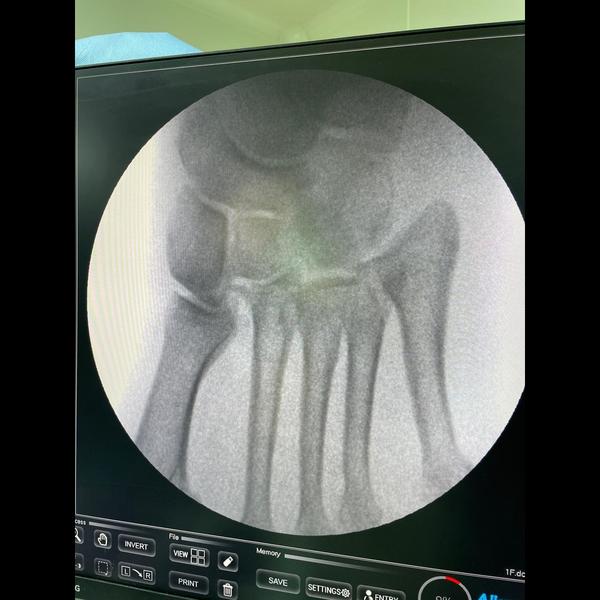

Type B2 complete Lisfranc injury

Intraop Images !